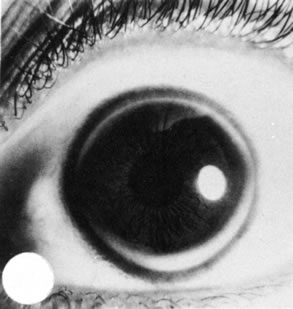

SCLEROCORNEA

Sclerocornea is a totally opacified cornea that shows clinical and histologic features of sclera. The condition often is bilateral. Superficial or deep vascularization of the tissue may occur. Associated clinical conditions include nystagmus, strabismus, aniridia, cornea plana, macular hypoplasia, horizontally oval cornea, and glaucoma.76 As described in Mieten's syndrome, sclerocornea may present with congenital cerebral dysfunction, deafness, cryptorchidism, pulmonary disease, brachycephaly, and defects of the face, ears, and skin. Sclerocornea may be inherited in an autosomal dominant pattern. It may result from intrauterine inflammation and other nonspecific causes.

Histologically, increased numbers of collagen fibrils with a variable collagen diameter occur in the normal corneal stroma. Descemet's membrane appears thin.77,78 Bowman's membrane may be absent.79

Sclerocornea has been associated with an interstitial deletion of the short arm of chromosome 6(46XY del[6 [p22 p24])80 and a microdeletion of Xp22.3.81,82 Recent evidence supports linkage to mutations in the distal arm of chromosome 6.80